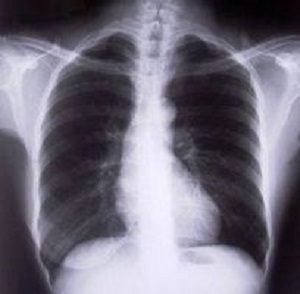

– Le risque de survenue ou d’aggravation de diverses maladies respiratoires. Il y a notamment la pneumonie, l’asthme, le syndrome d’apnée du sommeil ou encore une broncho-pneumopathie obstructive. Cette dernière est une pathologie des poumons se caractérisant par une obstruction progressive des voies respiratoires ;